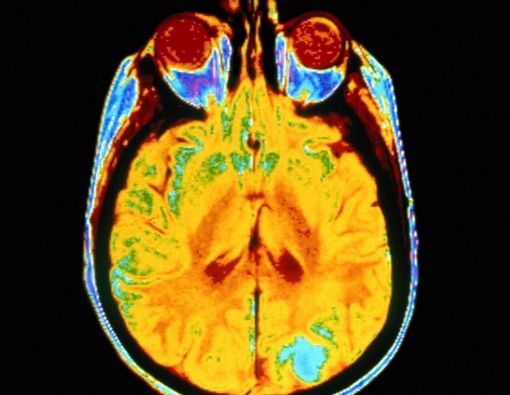

Kanker otak berawal dari sel abnormal pada otak dan bisa menyebar dengan cepat. Meski mematikan, penyakit ini bukan berarti tidak dapat sembuh atau punya peluang hidup. Hanya saja, ada risiko komplikasi kanker otak yang mungkin terjadi.

Dokter Arina Heidyana menjelaskan, “Komplikasi kanker otak bisa beragam. Mulai dari kesulitan untuk berbicara, gangguan pada ingatan, gangguan pendengaran, dan sebagainya.”